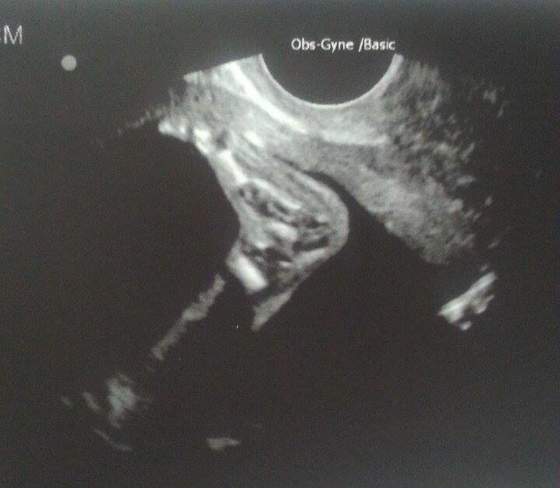

No więc Pani dr potwierdziła "dziewusię"

Dziś zaczynamy 22 tydzień. Mała waży 360 gram i ma się świetnie

Jest bardzooooo aktywna! Całe badanie fikała i wierzgała nóżkami i rączkami - cudny widok!! No i ciągle daje o sobie znać kopniakami

Mierzy ok 17 cm do pupy ale już ciężko było zrobić pomiar bo nie mieściła się w kadrze

No i z tego wszystkiego zapomniałam o mojej wczorajszej wizycieNo więc Pani dr potwierdziła "dziewusię"

Mam nawet rozmiar stópki hihi całe 3 cm

No i foteczki mojej gwiazdy :

Zobacz załącznik 709432Zobacz załącznik 709433